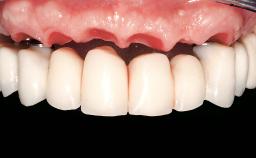

Prosthesis Type | RDP |

Defining Characteristics | Fully edentulous lower jaw to be rehabilitated with an implant-borne removable overdenture |